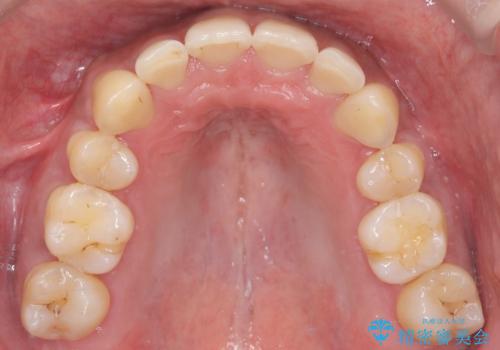

- 前歯のデコボコ(叢生)と、上下の歯の重なりが深い「ディープバイト(過蓋咬合)」を主訴にご来院されました。精密検査の結果、歯が並ぶスペースが不足しているため、上顎左右の小臼歯を抜歯することでスペースを確保し、全体の咬み合わせを改善する治療計画を立案しました。これにより、見た目の改善だけでなく、過度な咬み合わせによって生じる歯や顎への負担も軽減することを目指します。

今回の矯正治療では、まず歯が並ぶスペースを確保するため、上顎の小臼歯を抜歯しました。抜歯によってできたスペースを利用して前歯を奥へ移動させ、デコボコを解消。同時に、奥歯の咬み合わせを調整することで、深すぎた咬み合わせであるディープバイトも改善しました。治療の結果、長年気にされていた前歯のデコボコが解消され、理想的な歯並びに。さらに、正しい咬み合わせを獲得したことで、機能的にも安定した美しい口元になりました。